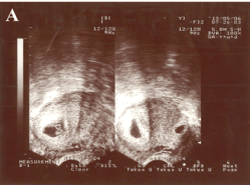

Figure 1. Transvaginal ultrasonography examination before selective embryo reduction. There were two gestational sacs in the uterine cavity, one (as shown the left one of the right portion) in the inferior portion of the uterus and the other (as shown the right one of the right portion) in the lower segment scar area of the anterior uterus, both with germ tubes and beating hearts.